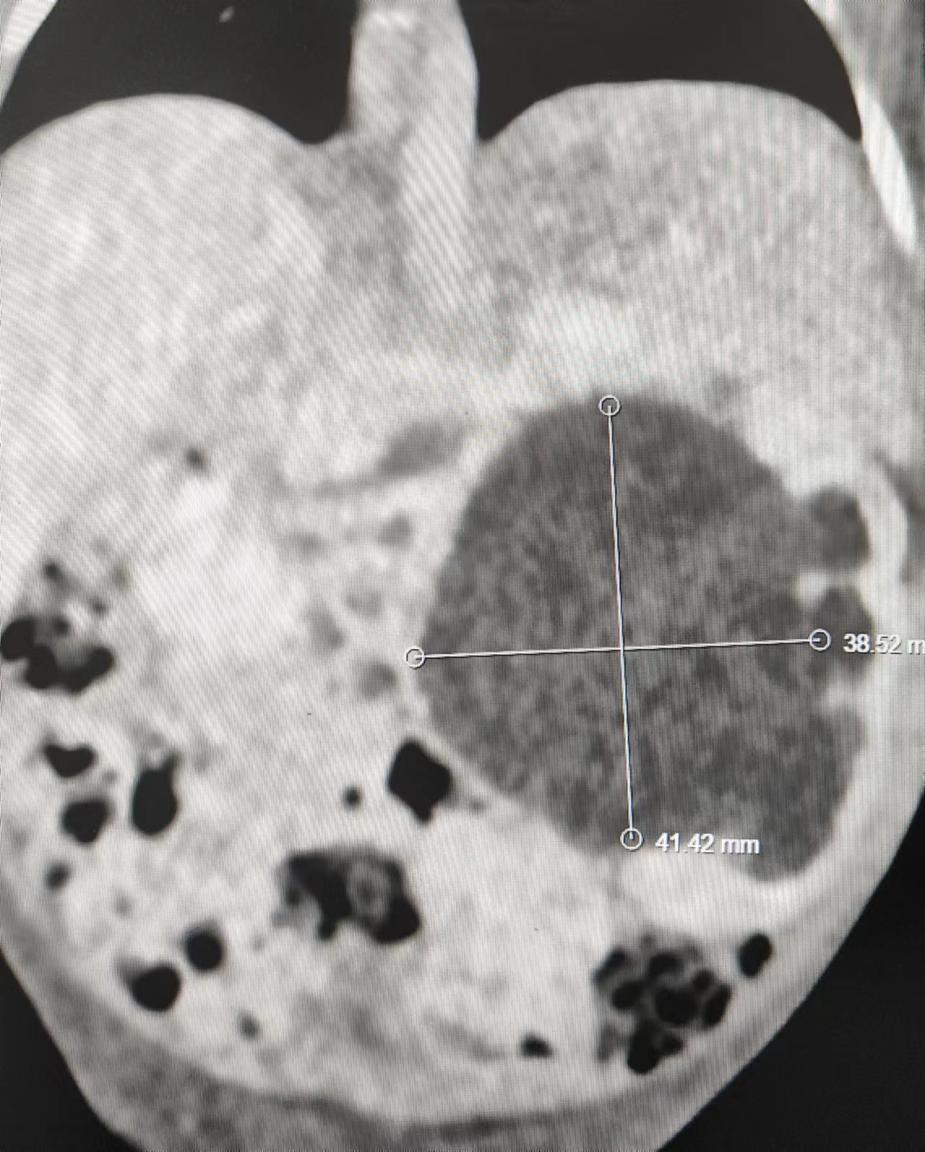

术前泌尿增强CT显示其左肾重度积水